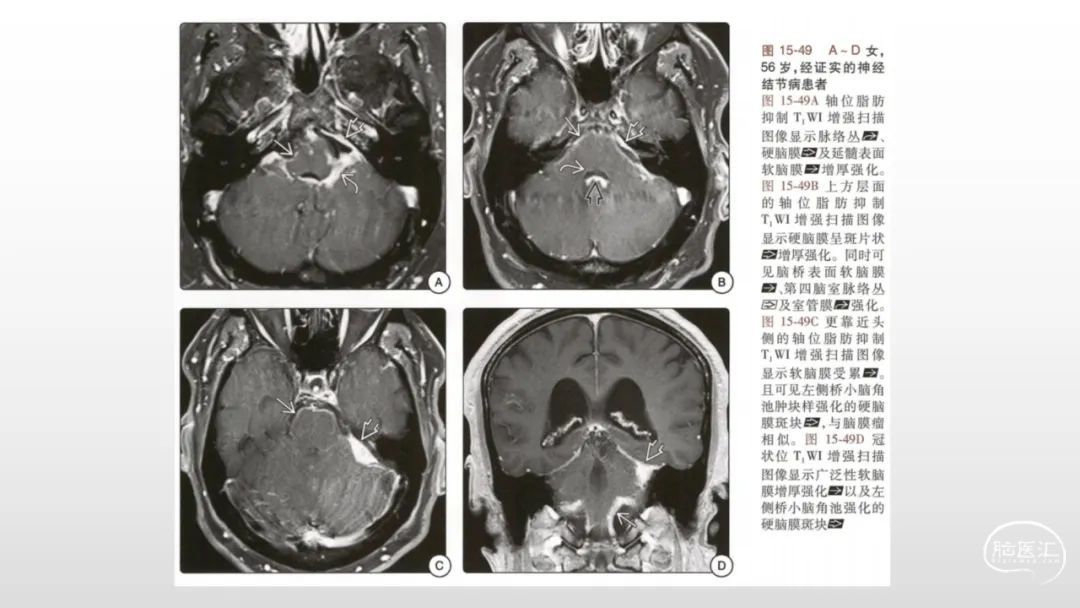

颅脑影像诊断基础知识讲座:脑膜病变